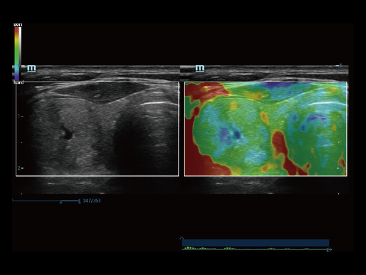

Oprócz uzyskiwania jako?ci obrazu typowego dla aparatów klasy premium, Resona 7 rozszerza mo?liwo?ci klinicznych badań USG dzi?ki rewolucyjnej funkcji V Flow, s?u??cej do oceny hemodynamiki naczyń, a tak?e najlepszej na rynku funkcji inteligentnego, automatycznego uzyskiwania p?aszczyzny na podstawie zestawów danych obj?to?ciowych 3D, umo?liwiaj?cej diagnozowanie stanu Centralnego Uk?adu Nerwowego u p?odu. Aparat Resona 7 ??czy w sobie najbardziej intuicyjn?, wielodotykow? obs?ug? za pomoc? gestów oraz wszystkie kluczowe funkcje kliniczne, co sprawia i? jest prawdziwym liderem we wprowadzaniu innowacji w ultrasonografii.